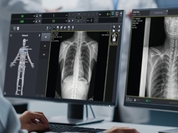

식품의약품안전처(처장 오유경)는 4월 1일, 흉부 X선 영상을 생성형 인공지능(AI)으로 분석해 텍스트 형태의 예비소견서를 자동 생성하는 디지털의료기기를 허가했다고 밝혔다. 이번에 허가된 제품은 흉수, 기흉, 폐부종, 폐결절, 심장비대, 활동성 결핵, 늑골 및 쇄골 골절 등 총 57종의 이상 소견을 분석해 영상의학과 전문의의 판독을 보조하는 기능을 갖췄다. 기존 AI 기반 디지털의료기기가 병변 위치 표시나 질환 유무, 중증도 분석 등 시각적 정보 제공에 머물렀다면, 이번 제품은 생성형 AI 기술을 활용해 영상 내 이상 소견을 종합적으로 해석하고 이를 텍스트 기반의 예비 판독문 형태로 직접 제시하는 것이 특징이다. 이는 국내 최초로 생성형 AI가 적용된 디지털의료기기 사례다. 임상시험에서는 흉부 X선 판독문을 대조군으로 설정하고 숙련된 영상의학과 전문의 5명이 비교 평가를 진행한 결과, 해당 제품이 실제 임상 현장에서의 전문의 판독과 유사한 수준의 정확도를 유지하는 것으로 확인됐다. 특히 이번 허가는 식약처가 지난해 시행한 「디지털의료제품법」에 따라 세계 최초로 마련한 ‘생성형 인공지능 의료기기 허가·심사 가이드라인’을 적용한 사례로, 임상시험 설계부터 허가까